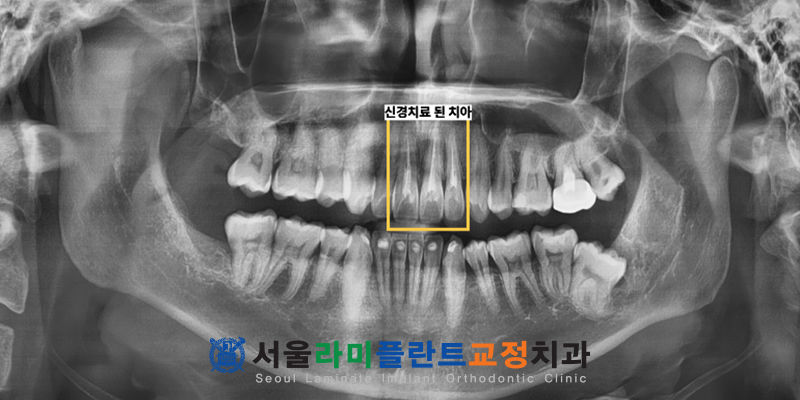

정밀 검진 결과 상악 중절치와

측절치에서 심한 변색이 관찰되었습니다.

x-ray를 촬영해서 확인해보니

과거에 신경치료를 완료한 치아였는데요.

이 상태에서 변색이 된 경우,

내부로부터의 원인이 크므로

내부 신경관을 통해 진행하는

실활치 미백이 필요했습니다.